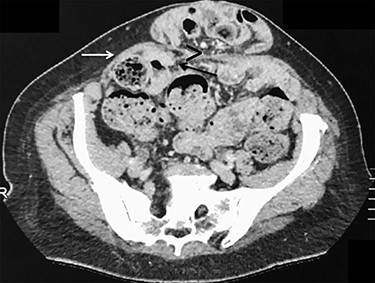

A 59-year old woman was referred with an infra-umbilical lump that had been progressively increasing in size and causing discomfort. A partly reducible midline ventral hernia was clinically diagnosed, containing loops of small bowel on CT-scan (Fig. 1). No other associated hernia defect was demonstrated. Laparoscopic repair was planned using a standard lateral trans-abdominal approach, with placement of the three ports at the level of the left anterior axillary line [4]. Incidentally, two associated ALHs were identified on each side of the main ventral hernia defect (Fig. 2). The peritoneum was incised transversally above the arcuate lines allowing both peritoneal folds to be completely reduced (Fig. 3). Peritoneum dissection was extended caudally with opening of the pre-peritoneal space, similar to a TAPP technique, for ideal mesh placement.

Contrast-enhanced CT imaging demonstrating an incarcerated ventral hernia containing small bowel loops. There is no evidence of associated arcuate line hernia (ALH) between the posterior rectus sheath and the rectus muscle. (A) Axial plane and (B) sagittal plane.